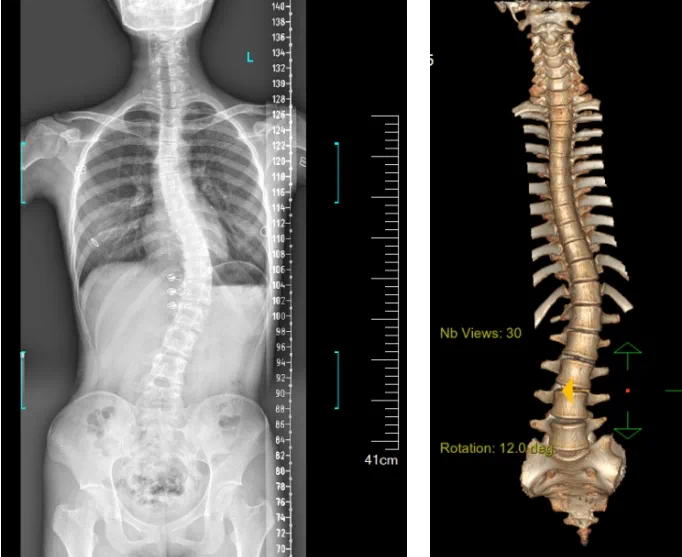

患者為一名16歲女孩,發(fā)現(xiàn)脊柱側(cè)彎1年,到南方醫(yī)院贛州醫(yī)院脊柱外科求診。經(jīng)查體,患者左右胸廓不對稱,雙肩等高,左肩胛骨隆起,背側(cè)呈“剃刀背”畸形,胸腰段棘突偏離正中線,胸腰段脊柱左側(cè)凸畸形;各棘突無壓痛及叩擊痛,右側(cè)腰部凹陷,胸腹及腰背部感覺正常。檢查發(fā)現(xiàn)患者特發(fā)性脊柱側(cè)彎,Lenke5C型,主胸彎51°。患者及家屬對外觀不滿意,為改善外觀及功能,要求手術(shù)矯形治療。

據(jù)悉脊柱側(cè)彎手術(shù)治療后可以保持軀干平衡,改善外觀并防止畸形進(jìn)一步發(fā)展。患者的生活質(zhì)量得到提高,進(jìn)而減少脊柱過度畸形可能帶來的疾病的發(fā)生率,外觀上的積極變化往往也能帶來患者心理與精神的積極變化。臨床上會綜合考慮患者的年齡、側(cè)彎程度、進(jìn)展趨勢、骨質(zhì)條件、鄰近節(jié)段情況、手術(shù)節(jié)段等因素,合理采用個性化的手術(shù)方式進(jìn)行治療。然而,由于脊柱神經(jīng)血管密布,手術(shù)操作相對復(fù)雜,手術(shù)難度高、風(fēng)險大,傳統(tǒng)脊柱側(cè)彎的手術(shù)方式往往有較高的神經(jīng)或脊髓損傷風(fēng)險。故此次科室決定開展機(jī)器人輔助導(dǎo)航下脊柱側(cè)彎矯形、植骨融合內(nèi)固定手術(shù)。術(shù)前,醫(yī)生團(tuán)隊在機(jī)器人多維度圖像融合智能手術(shù)規(guī)劃功能的輔助下,預(yù)先規(guī)劃了理想的置釘路徑。術(shù)中,天璣骨科手術(shù)機(jī)器人準(zhǔn)確遵循術(shù)前規(guī)劃,根據(jù)配準(zhǔn)結(jié)果,實(shí)時定位并準(zhǔn)確執(zhí)行置釘操作,所有導(dǎo)針均用電鉆置入,一次性成功,協(xié)助醫(yī)生順利完成手術(shù)。最終,在麻醉科、手術(shù)室密切配合下,歷時3小時成功完成側(cè)彎矯形術(shù),出血量僅500ml。術(shù)后,患者恢復(fù)良好,大小便及下肢神經(jīng)運(yùn)動感覺正常。